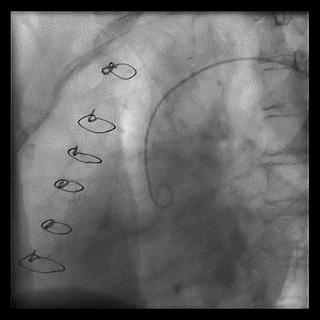

操作:升主动脉造影,寻找静脉桥血管

➢ CASE 3

AL1.0

➢ CASE 4

➢ CASE 5

升主动脉造影未见桥血管显影,原位血管造影也没发现竞争血流迹象,能够确定桥血管已闭塞,必要时能够借助冠脉CTA辅助诊断